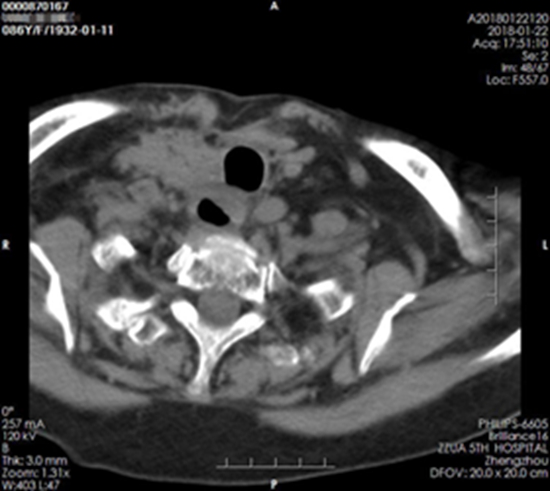

放疗科王晓瑜主任表示,检查结果显示患者的气管食管受侵,受压明显,管腔明显狭窄,考虑为甲状腺淋巴瘤局部复发,需要进行放射治疗。由于刘奶奶岁数较大,无形中增加了治疗的风险,王晓瑜主任在给诊疗组开会时多次强调既要保证放疗前的靶区勾画、物理计划及治疗中摆位的精准性,又要对放射治疗中出现的不良反应提前作出预估。

治疗前